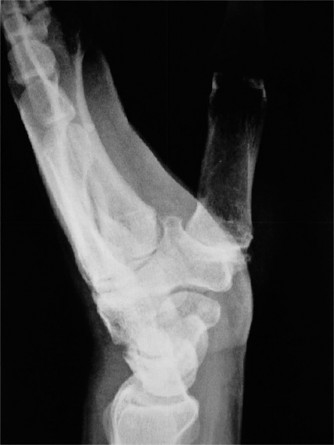

Standard posteroanterior (PA) and lateral radiographs of the wrist often fail to adequately visualize the pisotriquetral joint due to bony overlap from the distal pole of the scaphoid, the capitate, and the triquetrum itself. To properly assess this articulation, a 30-degree supinated AP view (the pisotriquetral view) is mandatory. In our first patient (referencing the classic Figure 3-10), this specific view reveals profound joint space narrowing, subchondral sclerosis, and prominent osteophyte formation at the pisotriquetral interface.

It is crucial to understand the osteology here. The pisiform is an atavistic, sesamoid bone. It is the only carpal bone that does not participate in the complex intercarpal kinematics of the proximal or distal rows. Instead, it lies entirely within the tendon of the flexor carpi ulnaris (FCU). The FCU-pisiform complex extends distally via robust ligamentous attachments: the pisotriquetral ligament, the pisohamate ligament, and the piso-5th metacarpal ligament. Notably, there is no piso-scaphoid ligament; the scaphoid resides on the entirely opposite side of the carpus.